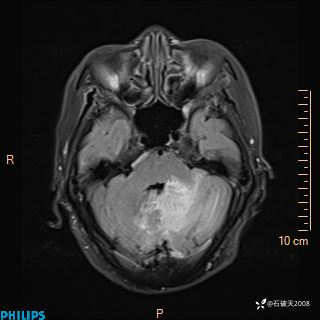

女 86岁 主 诉:乏力1月

现病史:患者1月前活动出现双下肢乏力,无头晕、头痛、恶心、呕吐、肢体活动不利,休息后缓解,间断断发作,症状进行性加重,在家口服药物治疗(具体不详),效差,为进一步诊治,来我院,门诊按“乏力”收住我科,患者自发病以来,神志清,精神稍差,饮食睡眠欠佳,大小便正常,体重未见明显改变。

FLAIR